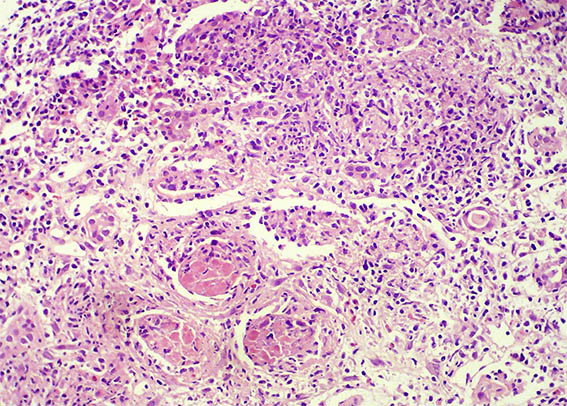

The patient is a 32-year-old man, kidney transplanted 18 months ago due to end-stage renal disease of unknown cause. A cellular rejection episode was evidenced in the first year. Good kidney function in the last control (16 post-transplantation months). Now in a new control the serum creatinine has risen to 1.9 mg/dL. Mild proteinuria and microscopic hematuria, no other abnormalities.

See the images of the renal allograft biopsy.

Figure 4. H&E, X400.